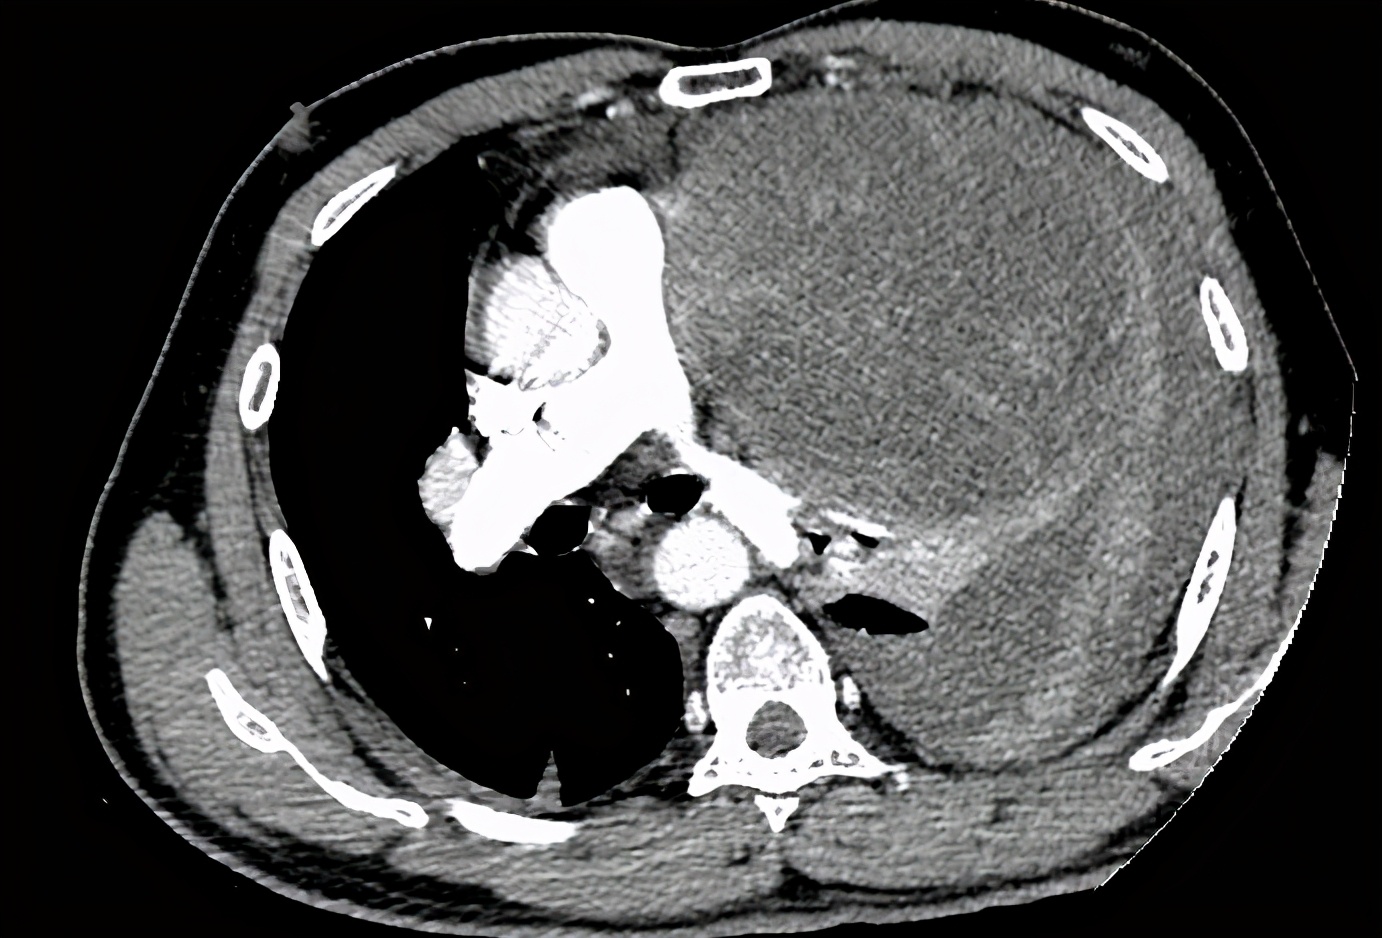

肿瘤几乎占据了左侧胸腔

几天前,家住枞阳的方师傅因感觉左侧胸闷及呼吸困难前往当地县医院就诊,经检查发现有一直径约20cm的巨大实质占位伴少量胸腔内积液,几乎占据了左侧胸腔,将心脏都挤压到右侧。由于患者病情复杂,当地医院建议转到上级医院救治。

转到安庆市立医院时,患者呼吸困难明显加重。该院心胸外科陈剑主任医师结合入院前后两次CT以及相关检查结果,诊断患者为左侧胸腔内巨大肿瘤破裂伴左侧胸腔内大出血,合并失血性休克、心肌损伤。“如此大的肿瘤在临床上非常少见,我也是第一次遇见”陈剑表示,当时肿瘤已经破裂出血,合并失血性休克为手术带来了巨大的风险,只有急诊手术切除肿瘤才有可能抢救患者的生命。”征得家属同意,与麻醉科、输血科充分沟通后,陈剑决定为方师傅做最后一搏。